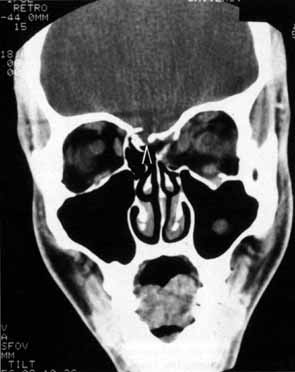

Anosmia caused by damage of cranial nerve I may be a helpful symptom of ethmoid or sphenoid sinus tumors invading the orbit (Fig. 20).44 Olfactory groove meningiomas and esthesioneuroblastomas may also present with anosmia prior to developing vision loss.45 Trauma that involves the orbit and is associated with anosmia should be considered a basilar skull fracture with potential for cerebrospinal fluid leak until proven otherwise (Fig. 21).

Fig. 20 A 13-year-old child presented with a 2-week history of sinusitis and anosmia. Her visual acuity decreased to to 20/400 1 day prior to admission. Computed tomography shows a large ethmoid tumor extending through the cribriform plate and optic canal. A rhabdomyosarcoma was diagnosed by biopsy.